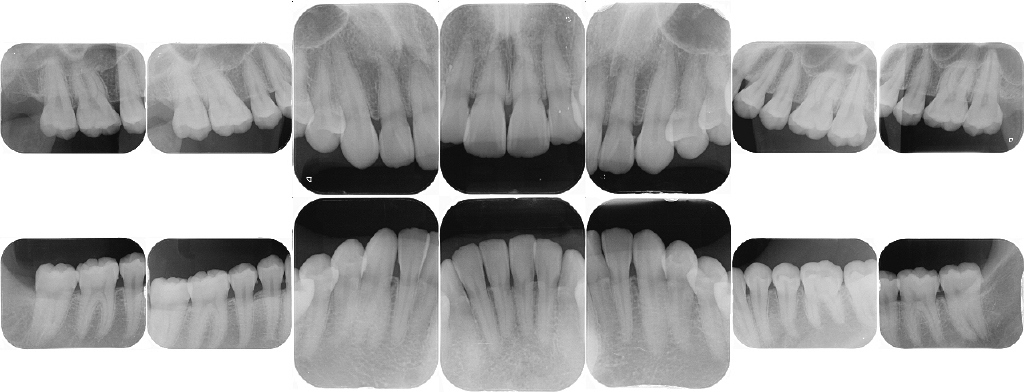

- X線デジタル写真

(10枚法+咬翼法4枚)

お口全体の撮影のほか、細部にわたって確認できる部分撮影も行います。